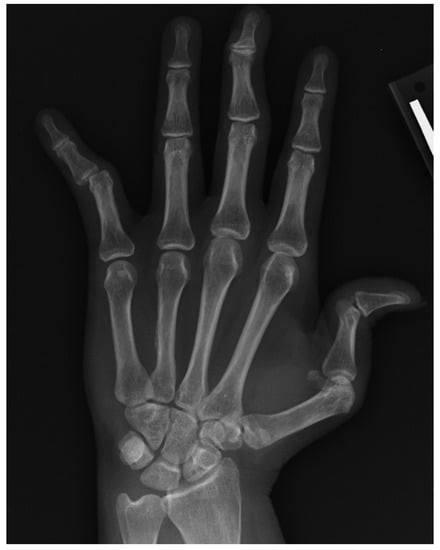

6. Erosive Osteoarthritis